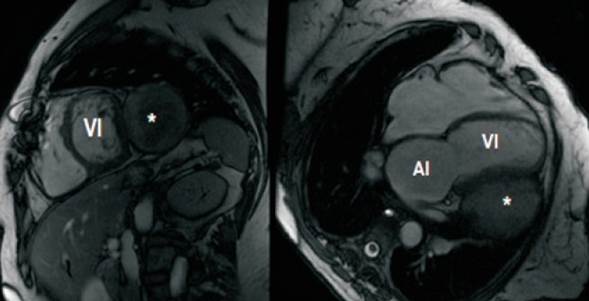

Se solicita resonancia magnética cardíaca (figura 4), que muestra compresión extrínseca de la pared lateral del VI por el tumor analizado, bien delimitado, paracardíaco izquierdo, que se encuentra por fuera del pericardio parietal, sin signos de infiltración. En la secuencia de realce tardío a nivel del septum interventricular en su porción basal y media se observa fibrosis de tipo no isquémica, lineal e intramiocárdica (CIV previa).

Figura 4: Cardiorresonancia magnética eje corto y cuatro cámaras en la que se evidencia masa que comprime la pared lateral del ventrículo izquierdo. VI: ventrículo izquierdo; AI: aurícula izquierda. * Masa sólida.